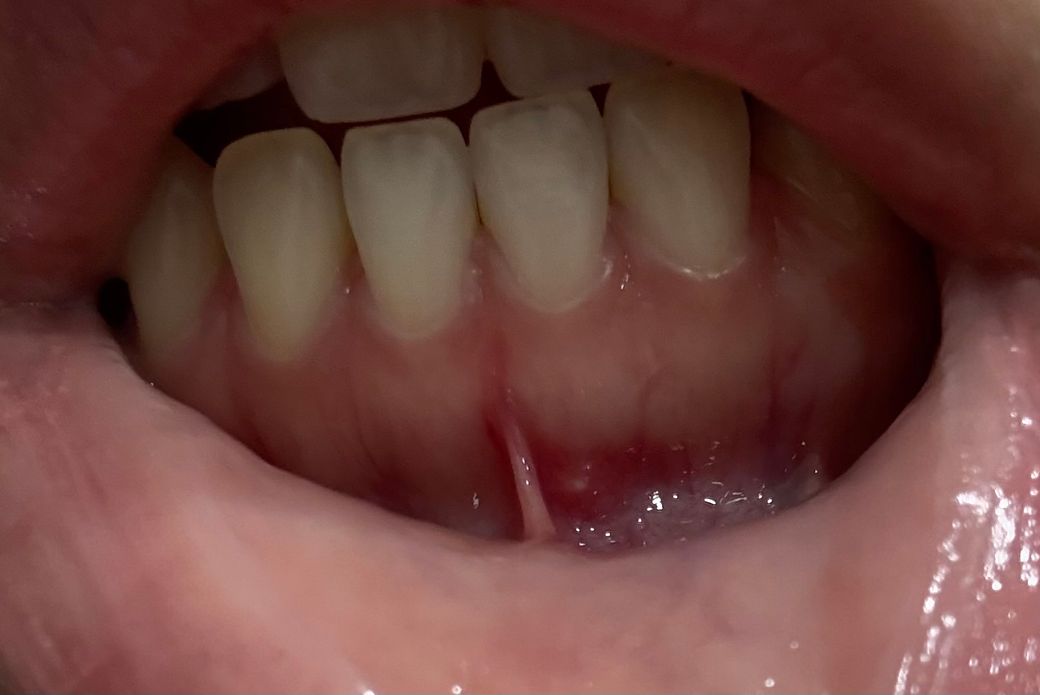

잇몸에 하얀 작은 염증(사진주의!!)

며칠 전부터 사진상 하얗게 염증이 올라온 딱 저 부분이 혓바늘이 난 것처럼 불편하더니 어제부터 뾰루지같이 염증이 올라왔습니다. 이게 잇몸질환인지 아니면 치아 뿌리같은 내부에 생긴 문제인지ㅠㅠ 처음 겪어보는 일이라 너무 신경쓰이네요. 며칠 경과를 지켜봐도 될까요 아니면 바로 치과에 달려가야 할까요??ㅠㅠㅠㅠㅠㅠ

• 1번 째 사진

사진에 보이는 부분에 자극을 받으면서 구내염이 생긴거 같습니다 시간이 지나면 괜찮아 지실꺼에요.

정확하게 확인하긴 어렵지만 구내염 또는 치근단 질환일 가능성은 높습니다. 구내염은 점막에 연조지게 손상이 생기고 감염이 되면서 생기는 증상입니다. 치근단 질환은 치아 내부에 신경이 감염이 되어 뿌리 쪽에 염증이 나오는 증상입니다. 치근단 질환일 경우에는 신경치료가 필요할 수 있으니 자세한 확인을 위해서 치과에서 진료를 받아보는 것을 권유드립니다.

치아 뿌리 염증일 가능성도 있기는 합니다. 며칠 지켜봐도 안 없어진다면 치과 가보심이 좋겠습니다.

심하지는 않습니다. 일시적일 가능성이 높습니다. 기다리면 저절로 없어질 가능성 높습니다. 아마도 지금 통증이나 큰 불편감은 없을 것으로 추정됩니다. 건드리지 않으면 저절로 가라앉을 것으로 보입니다.

사진만봐서는 정확한 진단이 어렵습니다 치과를 가보시는 것을 추천합니다 잇몸염증이든, 치조농양이든 치과에서 처치가 필요합니다